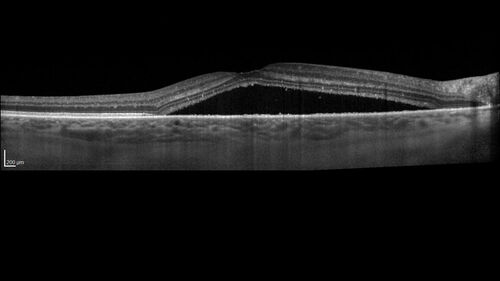

Serous Macular Detachment from Small Choroidal Melanoma

72 year old female misdiagnosed as CSR who had small choroidal melanoms.